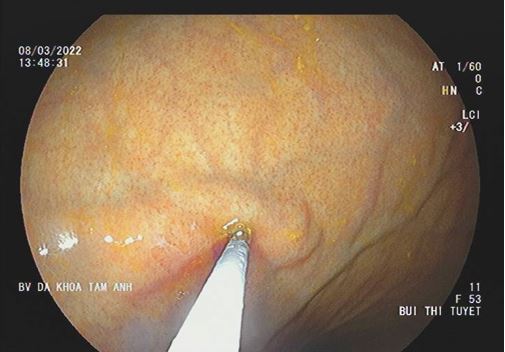

Nếu được phát hiện sớm, việc điều trị ung thư dạ dày cũng đơn giản hơn rất nhiều so với ung thư ở giai đoạn tiến triển hay giai đoạn muộn. Bệnh nhân không cần điều trị hóa chất, không phải chịu đựng phẫu thuật. Ở giai đoạn sớm, người bệnh chỉ cần tiến hành nội soi dạ dày để cắt hớt niêm mạc (Endoscopic Mucosal Resection- EMR) hoặc cắt tách niêm mạc (Endoscopic Submucosal Dissection – ESD), có nghĩa là tiến hành lấy toàn bộ vùng niêm mạc bị ung thư qua nội soi đường miệng với chất lượng sống tốt như người bình thường, đồng nghĩa với điều trị khỏi bệnh hoàn toàn.

Nội soi phóng đại từ 100 lần với NBI, BLI cho phép tầm soát ung thư thực quản dạ dày sớm và tầm soát polyp đại tràng.